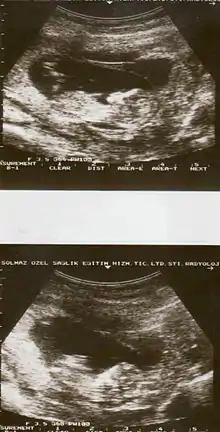

| Diagnostic method | Based on symptoms, ultrasound[1] |

Placental abruption is suspected when a pregnant mother has sudden localized abdominal pain with or without bleeding. The fundus may be monitored because a rising fundus can indicate bleeding. An ultrasound may be used to rule out placenta praevia but is not diagnostic for abruption.[8] The diagnosis is one of exclusion, meaning other possible sources of vaginal bleeding or abdominal pain have to be ruled out in order to diagnose placental abruption.[5] Of note, use of magnetic resonance imaging has been found to be highly sensitive in depicting placental abruption, and may be considered if no ultrasound evidence of placental abruption is present, especially if the diagnosis of placental abruption would change management.[16]